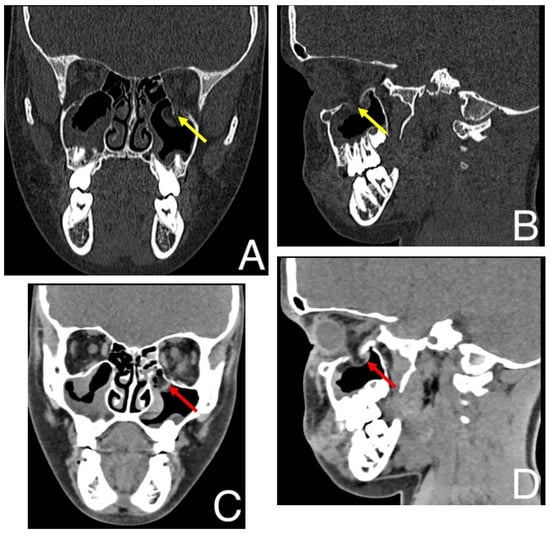

►▼

The study reports a diagnostic challenge involving an inflammatory lesion mimicking a brown tumor. A 23-year-old male patient was referred for treatment of a cystic lesion in the left frontal process of the maxilla and ethmoid region. The leading symptoms were hemoptysis and

The study reports a diagnostic challenge involving an inflammatory lesion mimicking a brown tumor. A 23-year-old male patient was referred for treatment of a cystic lesion in the left frontal process of the maxilla and ethmoid region. The leading symptoms were hemoptysis and chronic sinus inflammation. Endoscopic surgery was performed under general anesthesia, including curettage and drainage of the lesion into the middle nasal meatus. Histopathological examination revealed chronic inflammatory and fibrotic changes with hemosiderin deposits and CD68(+) histiocytes, findings that could suggest a brown tumor. However, subsequent laboratory investigations excluded this diagnosis. Postoperative healing was uneventful, with complete resolution of symptoms. This report highlights the importance of distinguishing inflammatory from metabolic bone lesions in the paranasal sinuses and underscores the critical role of histopathological evaluation in differentiating true neoplasms from inflammatory pseudotumors.

Figure 1